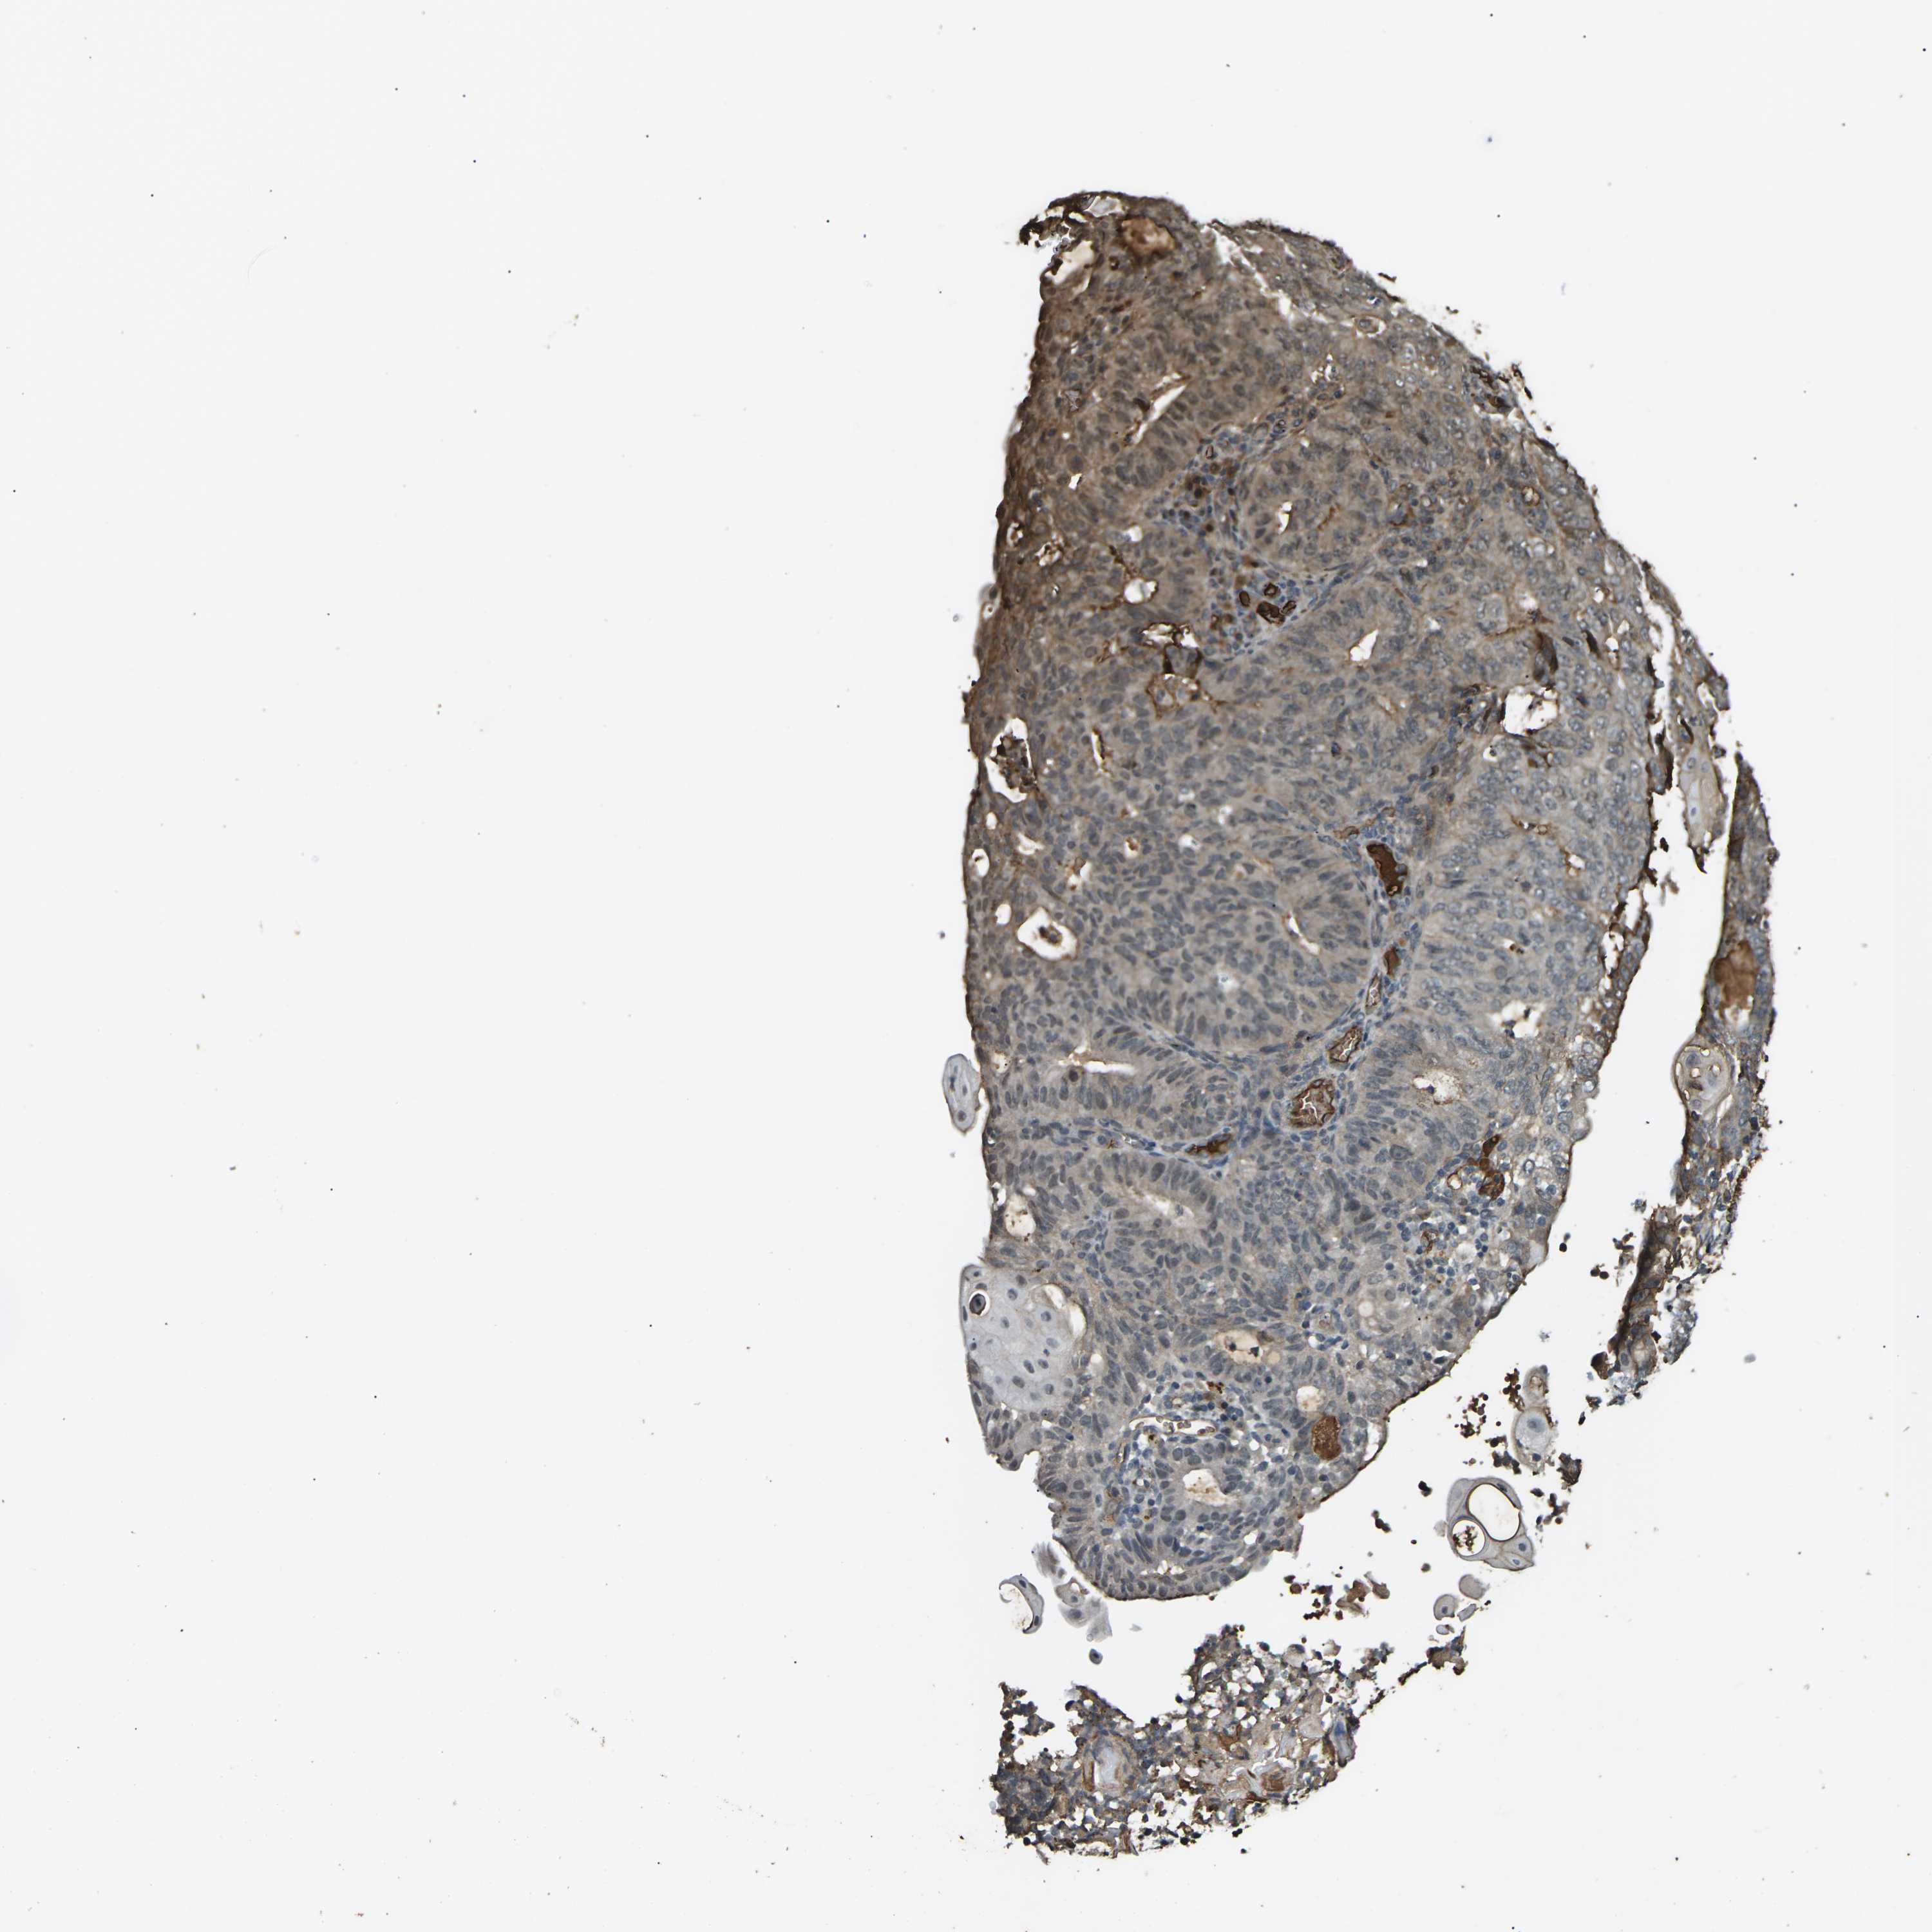

ENDOMETRIAL CANCER - Protein expressioni

A mouse-over function shows sample information and annotation data. Click on an image to view it in a full screen mode. Samples can be filtered based on level of antibody staining by selecting one or several of the following categories: high, medium, low and not detected. The assay and annotation is described here.

Note that samples used for immunohistochemistry by the Human Protein Atlas do not correspond to samples in the TCGA dataset.

Antibody stainingi

Antibody staining in the annotated cell types in the current human tissue is reported as not detected, low, medium, or high, based on conventional immunohistochemistry profiling in selected tissues. This score is based on the combination of the staining intensity and fraction of stained cells.

Each image is clickable and will lead to virtual microscopy that enables deeper exploration of all samples and also displays staining intensity scores, fraction scores and subcellular localization as well as patient and tissue information for each sample.

Antibody HPA026863

Antibody CAB011705

Staining

High

Medium

Low

Not detected

Intensity

Strong

Moderate

Weak

Negative

Quantity

>75%

75%-25%

<25%

None

Location

Nuclear

Cytoplasmic/membranous

Cytoplasmic/membranous,nuclear

Adenocarcinoma, NOS

Adenocarcinoma, metastatic, NOS